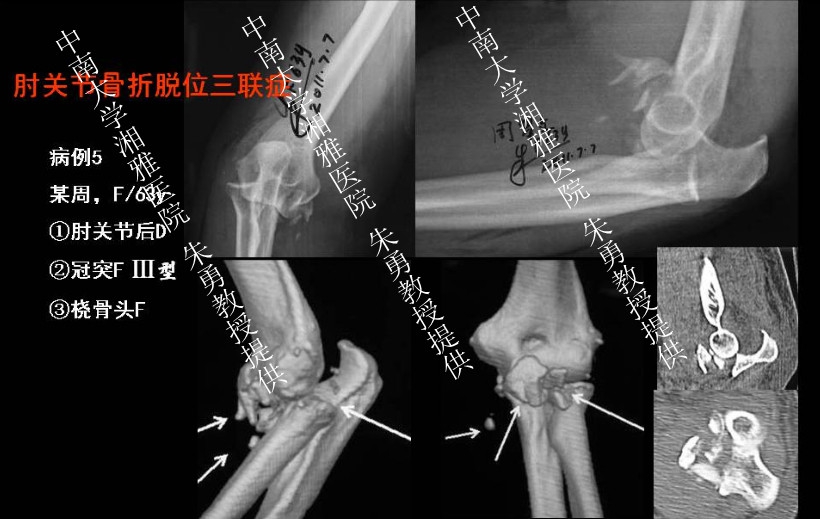

肘关节是人体内在稳定性最强的关节之一,骨性结构和软组织结构复杂。单纯肘关节脱位时没有骨折,但常伴有关节囊、韧带和其他软组织的损伤。复位后常比较稳定,很少出现关节不稳定和退变。相反,复杂的肘关节脱位是关节囊、韧带损伤的同时合并一处或多处骨折,治疗比较困难。为此,骨科在线创伤主编、北京大学人民医院付中国教授特邀请中南大学湘雅医院朱勇教授分享他治疗复杂肘关节脱位的心得,在此也希望广大骨科同仁踊跃投稿(典型病例和学术文章),来稿请发至:orth@orthonline.com.cn